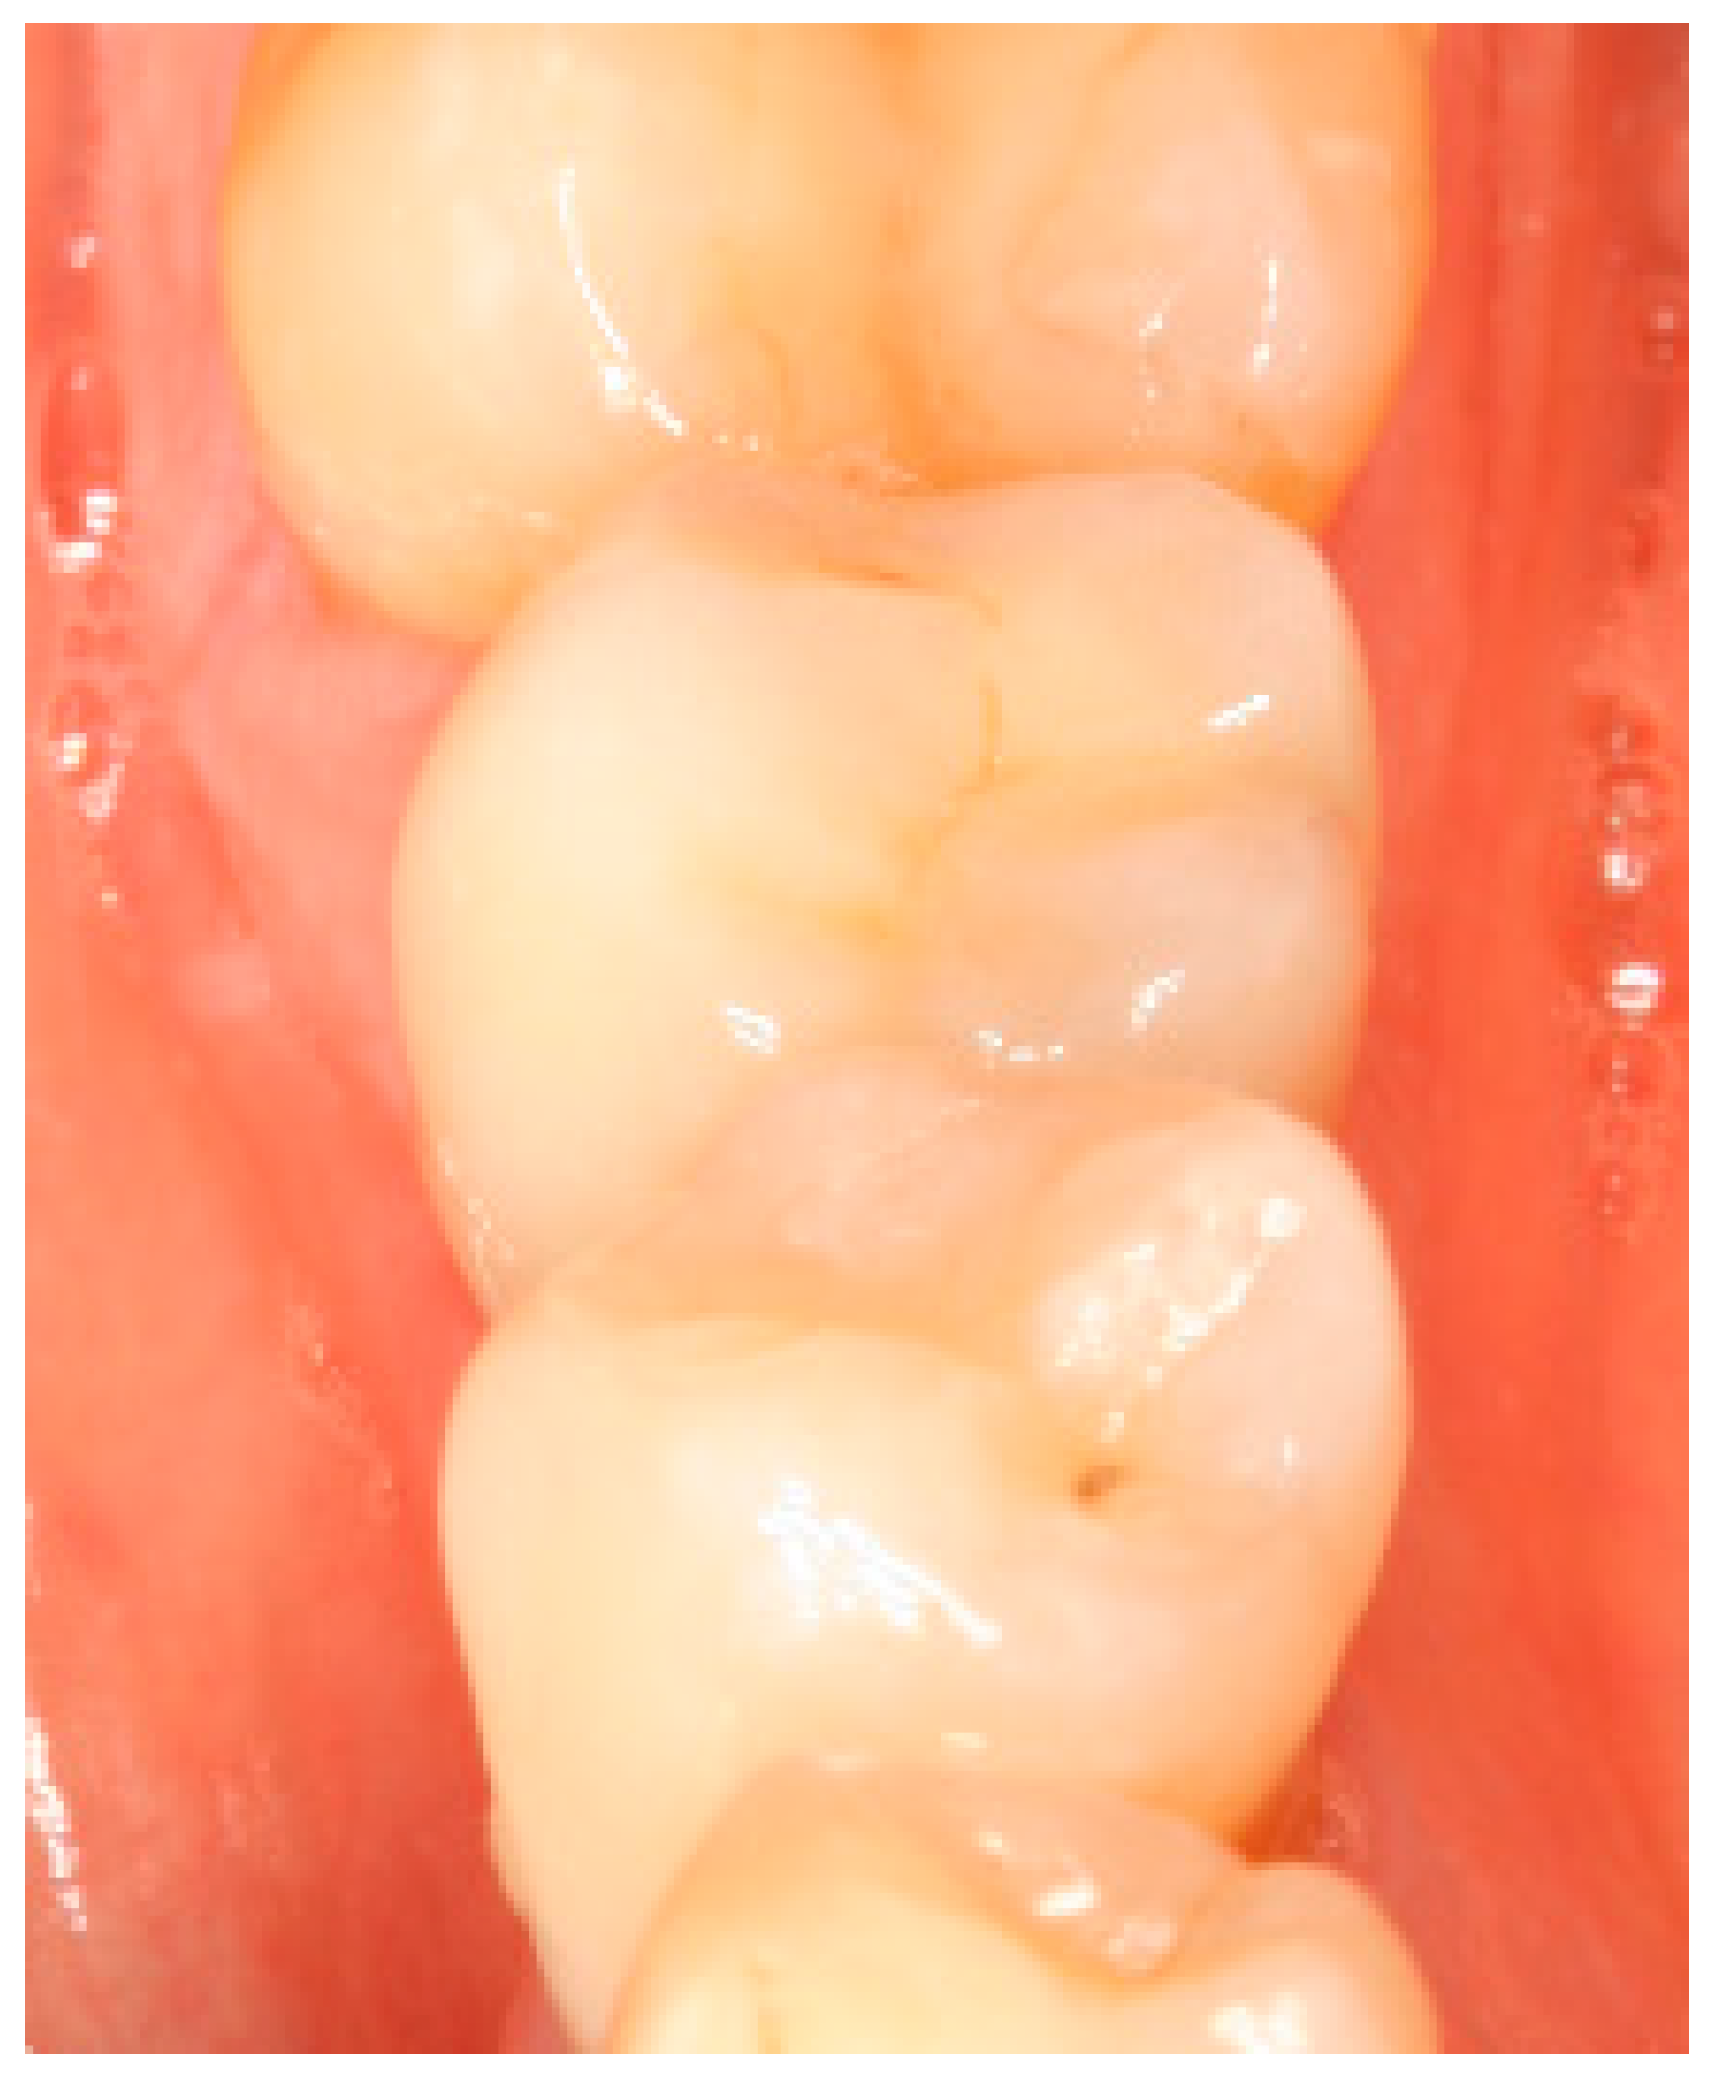

Appendix A. Exemplary Photographs and Radiographs from a Patient at Different Examination Time Points and a Positive Outcome

Appendix B. Exemplary Photographs and Radiographs from a Patient at Different Examination Time Points and a More Negative Outcome